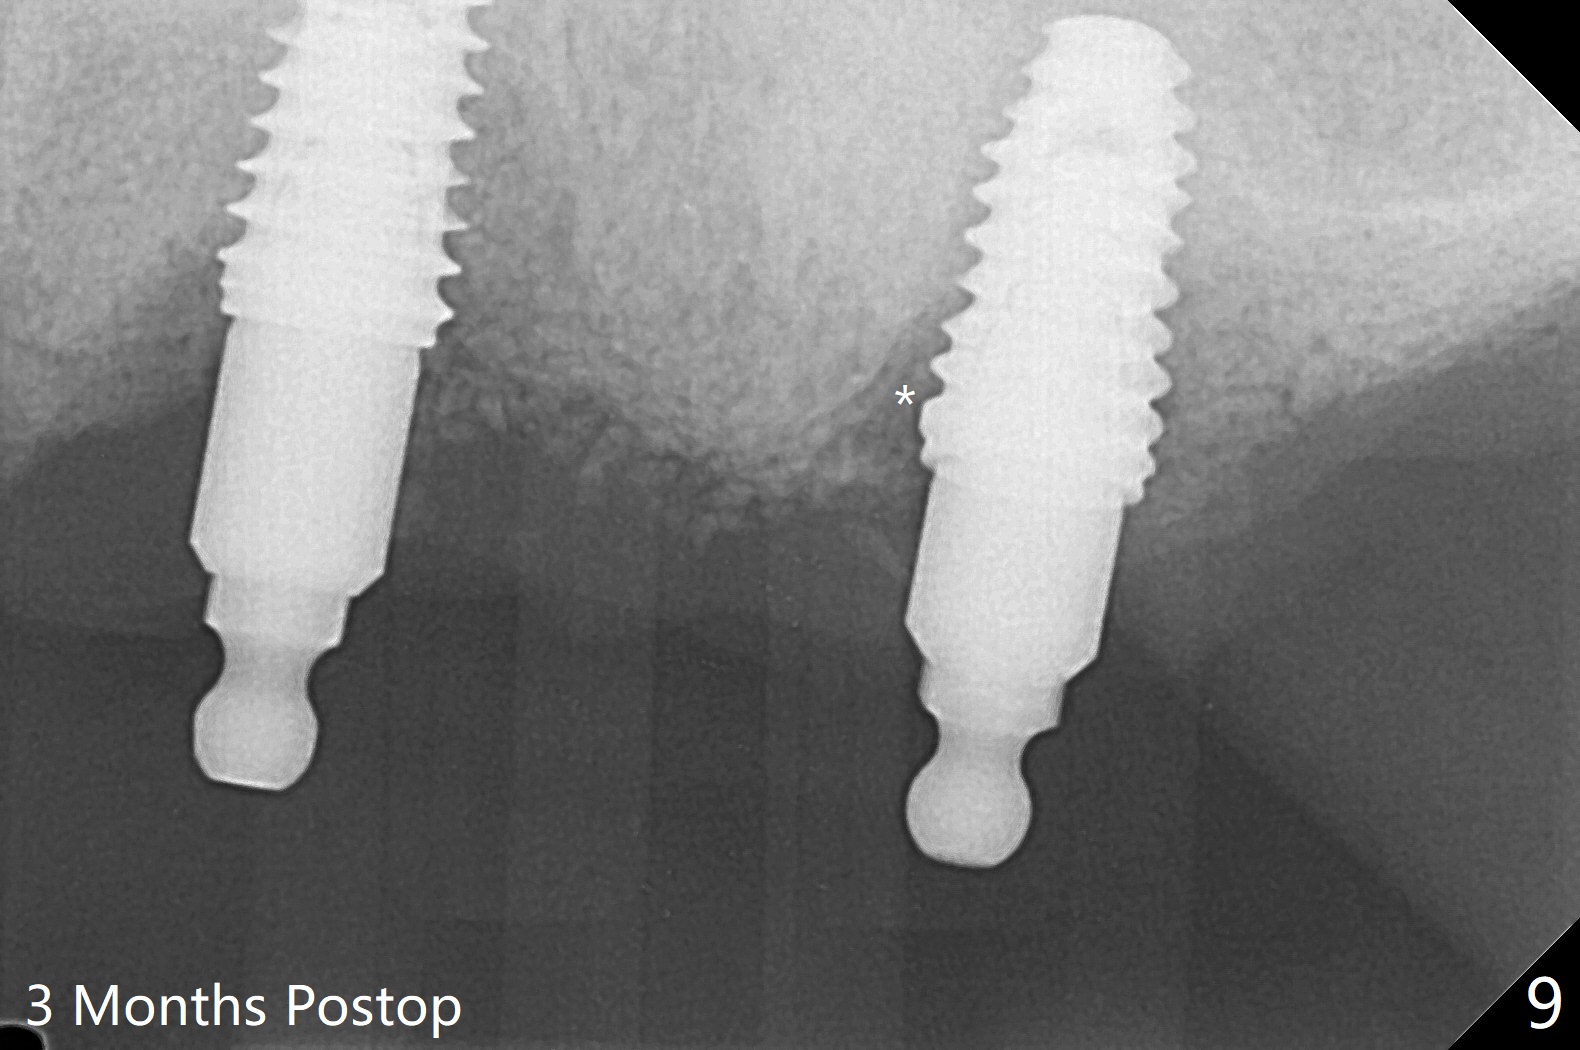

Osteotomy at #13 starts blindly (no incision or tissue punch) with bone expanders. After insertion of parallel pins, intraop CT shows that it is palatal with apparently buccal low bone density (Fig.1); the osteotomy for implant (Fig.2 green) should be shifted buccal and tilted mesial (red, parallel to #11) with incision. In contrast the position, trajectory and depth (Fig.3 <) of the initial osteotomy are acceptable at #11. The implant will be placed as it is (Fig.4). After taking a postop PA (Fig.5), the implant at #11 is placed a little deeper to make sure its slightly subcrestal placement (including distal incision at #11). Following placement of 3.5x4 and 3 mm ball abutments at #11 and 13, cortical allograft with PRF is placed around the implants, especially buccal (Fig.6,7 <). After suturing, the profile of the ball abutments is too low for RPD retention. Due to gravity other than bone density, the number of ball abutments for the maxilla should be more than for the mandible. Soft reline is done to the patient's satisfaction. The retention of the upper RPD after soft reline is satisfactory without pain 7 days postop (Fig.8). The implant at #13 is loose nearly 3 months postop (Fig.9 *: bone loss). The implant is removed while the ball abutment is untightened; the sinus floor is present. It appears that a longer and larger implant is necessary; a 4.5x10 mm dummy implant is unable to be seated deep or achieve primary stability (Fig.10). After sinus lift with 3 mm Bicon osteotome without bone graft, the dummy implant accomplishes the 2 tasks mentioned above (Fig.11). However there is no corresponding definitive implant in stock. Implant system needs to be changed; with a change in implant driver, the depth control is lost. The final implant is placed deep (Fig.12). With back up, stability is lessened; a healing screw is placed; with collagen plug, the wound is sutured (Fig.13). The wound heals 1 week postop (Fig.15). The RPD is soft relined. Retention from the ball abutment at #11 is apparently critical. The RPD and #11 implants (4 months postop) are stable, while the wound at #13 heals 1.5 months postop (Fig.15). There is space around the implant 5.5 months postop (Fig.16 *). The 5x10mm SM implant is found to be loose upon uncover and removed. After debridement, 5.3x8 mm SM and 5.5x9 mm IBS dummy implants are inserted without stability, while 6x9 mm definitive one with stability (Fig.17). Cortical allograft is placed in deficiency areas (*). The osteotomy has no roof (sinus floor), but the sinus membrane is intact. Small amount of bone graft (Fig.18 *) is placed before implantation. There appears to be bone around the new implant (Fig.19 (3D sagittal section) *).